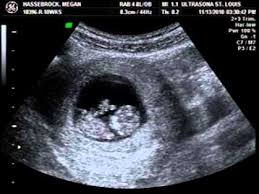

10 Weeks Pregnant Ultrasound, My Ultrasound At 10 Weeks Pregnant Baby Hardnett 2016 Youtube - Bloating can still be a contributor to a perceived bump and not everyone will see a baby bump at 10 weeks.. Pregnancy week 10 learn what is happening with your baby's development in week 10. At 10 weeks pregnant, you're getting close to the end of your first trimester. At this stage, the baby is growing even more rapidly! So, there's a chance that you've either already had the ultrasound, or that you'll be having it soon. You are 10 weeks and 2 days pregnant.

Your partner to ask any questions he may have, get to know your healthcare provider, hear the heartbeat, and see the baby via ultrasound. 10 week pregnant ultrasound can determine the exact site of pregnancy and if there is ectopic pregnancy it can be diagnosed. At 10 weeks pregnant, you're getting close to the end of your first trimester. 10 weeks 3 days pregnant. A month later hemmorage healed on it own and was back to normal activity.

But if you are feeling some uncomfortable symptoms, things may seem like they're dragging. You are 11 weeks exactly pregnant. An ultrasound scan at this stage would show your baby making little, jerky movements. Your 10 weeks pregnant belly. A guide on pregnancy at 10 weeks with information on what to expect, baby development, and symptoms. You are 10 weeks and 2 days pregnant. Meanwhile, your baby is growing and hitting a big milestone at the end of this week. In the 10 weeks pregnant ultrasound, you would notice that your baby's body parts are now visible more clearly.

A guide on pregnancy at 10 weeks with information on what to expect, baby development, and symptoms. Meanwhile, your baby is growing and hitting a big milestone at the end of this week. At 10 weeks of pregnancy, the foetus weighs about 4gm and measures around 3.1cm from crown to rump. The cvs (chorionic villus sampling), performed between weeks 10 and 13, uses an ultrasound to determine the placenta's location. Plus, find out what to expect at your first ultrasound , and why you may be experiencing the pregnancy glow. Avoid wearing tight and constricting clothes. You are 10 weeks and 2 days pregnant. At this stage, the baby is growing even more rapidly! Either way, at ten weeks pregnant, you are about a quarter of the way through your pregnancy. So, there's a chance that you've either already had the ultrasound, or that you'll be having it soon. Bereichern sie ihr leben durch unvergessliche yoga erlebnisse. Just was told no lifting, no sex, and no other strenuous work until approved by doctor. But if you are feeling some uncomfortable symptoms, things may seem like they're dragging.

You may be wondering when those pesky early pregnancy symptoms will start to fade or getting ready to share your big news with the world. This device is kind of like a microphone placed on the belly. Pregnancy symptoms & belly pictures. But if you are feeling some uncomfortable symptoms, things may seem like they're dragging. Ultrasounds are usually done in the first trimester to confirm a viable pregnancy, confirm the heartbeat, and confirm molar or ectopic pregnancies and also to assess abnormal gestation. A month later hemmorage healed on it own and was back to normal activity. 10 weeks 3 days pregnant. Ultrasound image of identical twins at 10 weeks, these babies share the same sac. By conducting a scan, she will be able to identify whether or not your baby is developing normally. Avoid wearing tight and constricting clothes. Pregnancy week 10 learn what is happening with your baby's development in week 10. His toes and fingers have taken a distinct form and started developing fingernails as well. At 10 weeks of pregnancy, the foetus weighs about 4gm and measures around 3.1cm from crown to rump.